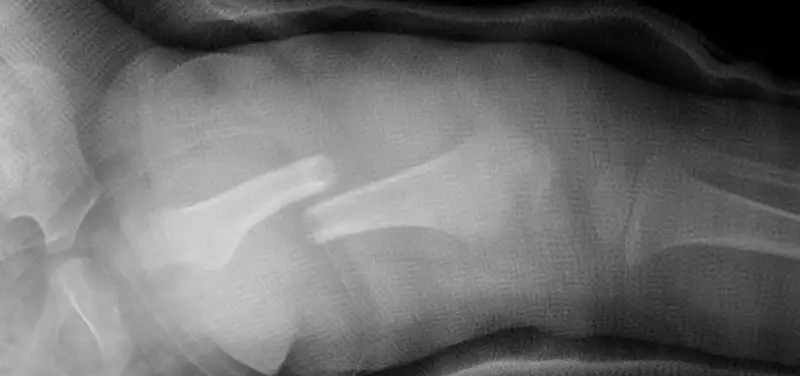

Below, there are several images of a displaced fracture through the femur. The bone breaks and moves, and the two pieces are not lined up straight. The blood clot surrounding the new fracture (Day 1 and 1 week) is not well seen. See how new bone forms around the fracture (1 month and 6 weeks) and over time is remodeled back into an almost normal appearance (10 months).